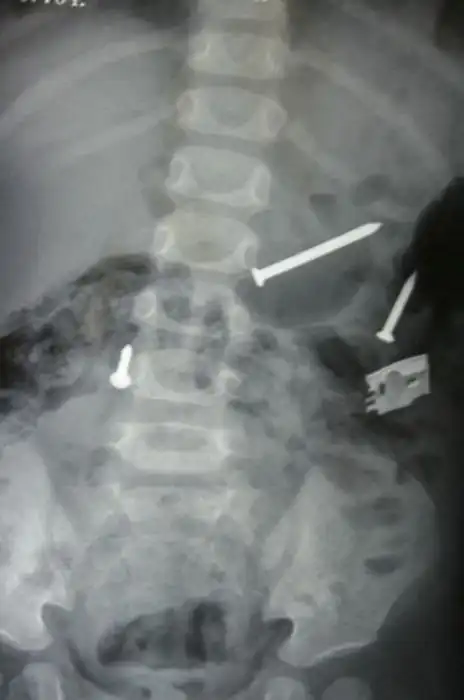

Порой даже не верится, с какими странными и необычными повреждениями в травматологию могут поступить пострадавшие. Всю эпичность профессии врачей травматологии могут с легкостью подтвердить рентгеновские снимки.

Жуткие рентгеновские снимки